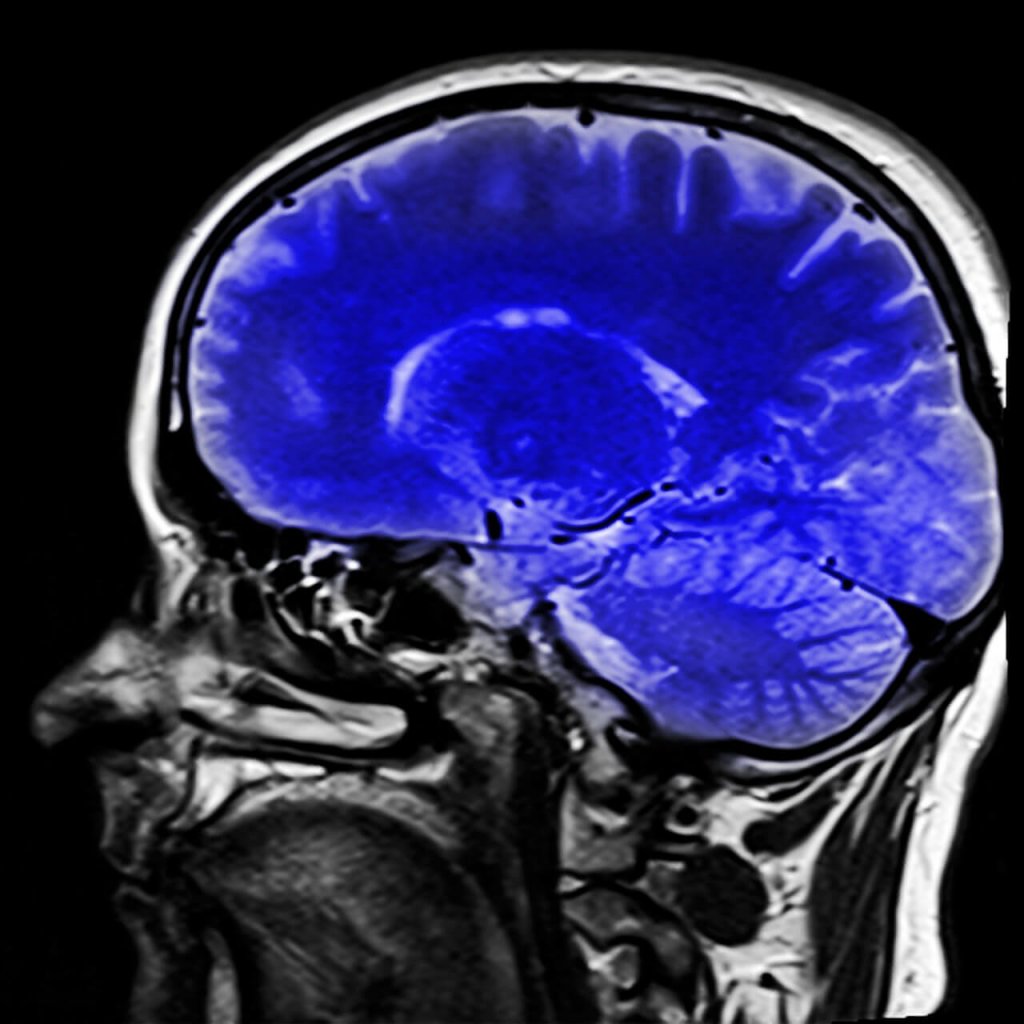

Existem alguns testes neurológicos que ajudam no diagnóstico. A ressonância magnética pode mostrar o tipo de lesão cerebral que pode apontar para a síndrome.